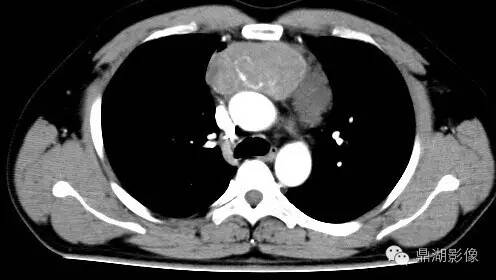

纵隔生殖细胞肿瘤(卵黄囊瘤)CT表现

影像表现:前纵隔见巨大囊实性肿块,形态不规则,实性部分可见点状钙化灶,病灶周围脂肪间隙消失,增强扫描病灶持续性不均匀明显强化. 医学百科网 | YxBaike.Com

探查见:前上纵隔肿物,升主动脉、上腔静脉前方,10×10cm大小,质硬,与上腔静脉无名静脉粘连紧密,无明显外侵,左右分别呈囊肿样,左侧6×5cm大小,右侧2×3cm大小。 医学百科网 | YxBaike.Com

1.(前纵隔)恶性肿瘤,结合组织学形态及免疫组化,考虑生殖细胞肿瘤(卵黄囊瘤)。送检(纵隔淋巴结)见癌转移(1/1)。 医学百科网 | YxBaike.Com

疾病总结:卵黄囊瘤又称内胚窦瘤,是一种由胚外结构—卵黄囊发生的高度恶性生殖细胞肿瘤。体积一般较大,结节分叶状,边界不清。切面灰黄色,呈实体状,局部可见囊腔形成,可有局部出血坏死。多发生于儿童及青年,常发生于性腺,原发于纵隔者较为罕见,且多在前纵隔。本病无特异症状,X线胸片及CT检查可见前纵隔巨大占位。年轻、病灶大、囊变,易侵犯周围,AFP高是特点,因为卵黄囊瘤可以产生甲胎蛋白(AFP),故本病病人血清中AFP的水平升高(>500U/ml),血清中AFP水平的测定对于诊断、治疗及预后有指导意义。